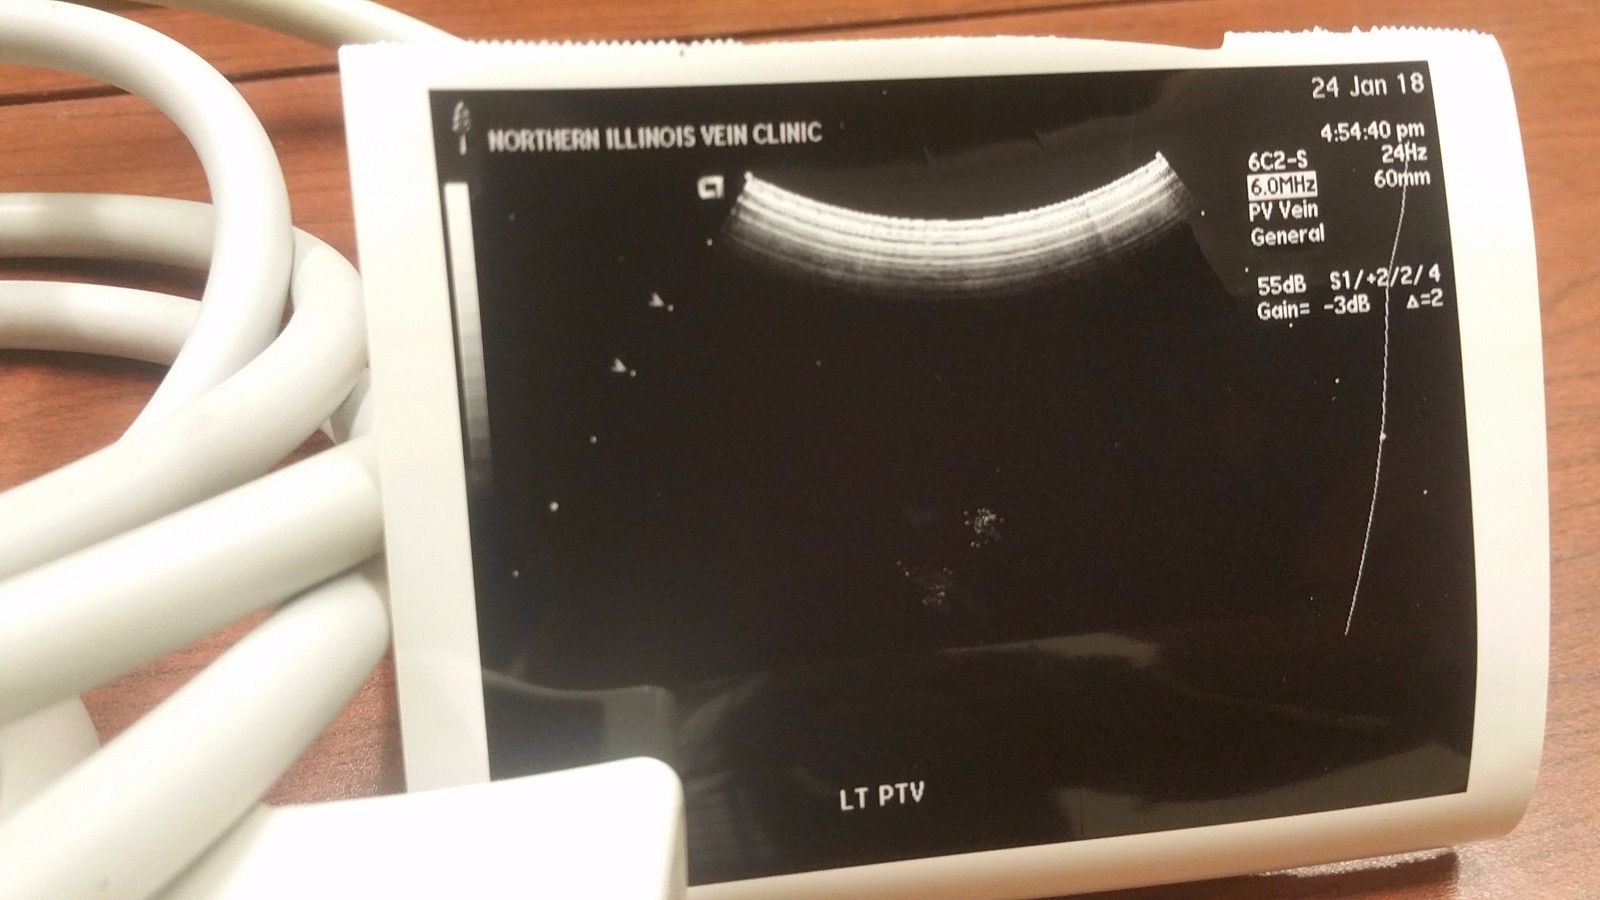

Acuson 6C2 Ultrasound Probe Transducer

The Acuson 4C1 Ultrasound Transducer Probe is a high-performance convex array probe designed for a wide range of clinical applications, including abdominal, obstetric, and gynecological imaging. Engineered for superior image clarity and deep tissue penetration, this transducer ensures accurate diagnostics with high-resolution imaging. Compatible with select Acuson ultrasound systems, the 4C1 probe offers excellent reliability and durability for continuous medical use. Its ergonomic design provides ease of handling, making it an essential tool for healthcare professionals seeking precision and efficiency in patient diagnostics. Whether replacing an existing transducer or upgrading your ultrasound equipment, this probe guarantees seamless integration and optimal performance. Each unit is tested and verified for quality assurance, ensuring consistent results in demanding medical environments. Available for fast shipping and competitive pricing, the Acuson 4C1 Ultrasound Transducer Probe is a trusted choice for professionals looking for accuracy and reliability in diagnostic imaging. Contact us today for pricing and availability.